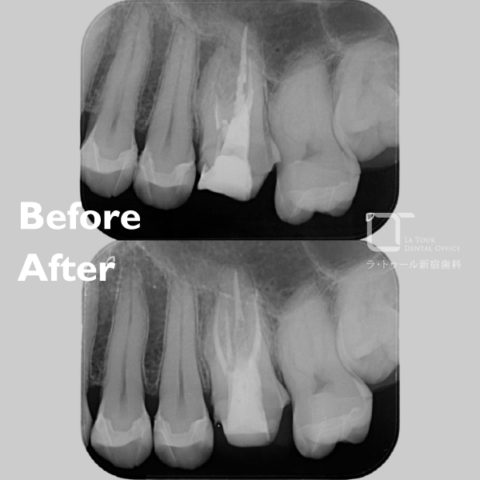

セラミック治療の治療例です。「以前、他院で治療した前歯の被せものの色味が不自然で気になる。また、被せものを入れてから歯茎が腫れるようになった。」とのことでご相談に来院されました。口腔内を確認したところ、セラミックの色が周囲の歯と調和しておらず、歯と歯茎の境目(マージン)部の適合が十分でないため、歯茎の炎症が起きている可能性が考えられました。当院にて、装着されていたセラミックの被せものを一度外し、歯茎の状態を確認したうえで、周囲の歯と自然になじむ色調のセラミックの被せものを新しく作り直しました。治療後は歯茎の腫れも落ち着き、前歯の色も周囲の歯となじみ、自然な見た目になりました。

治療前と治療後の比較

治療前

治療後